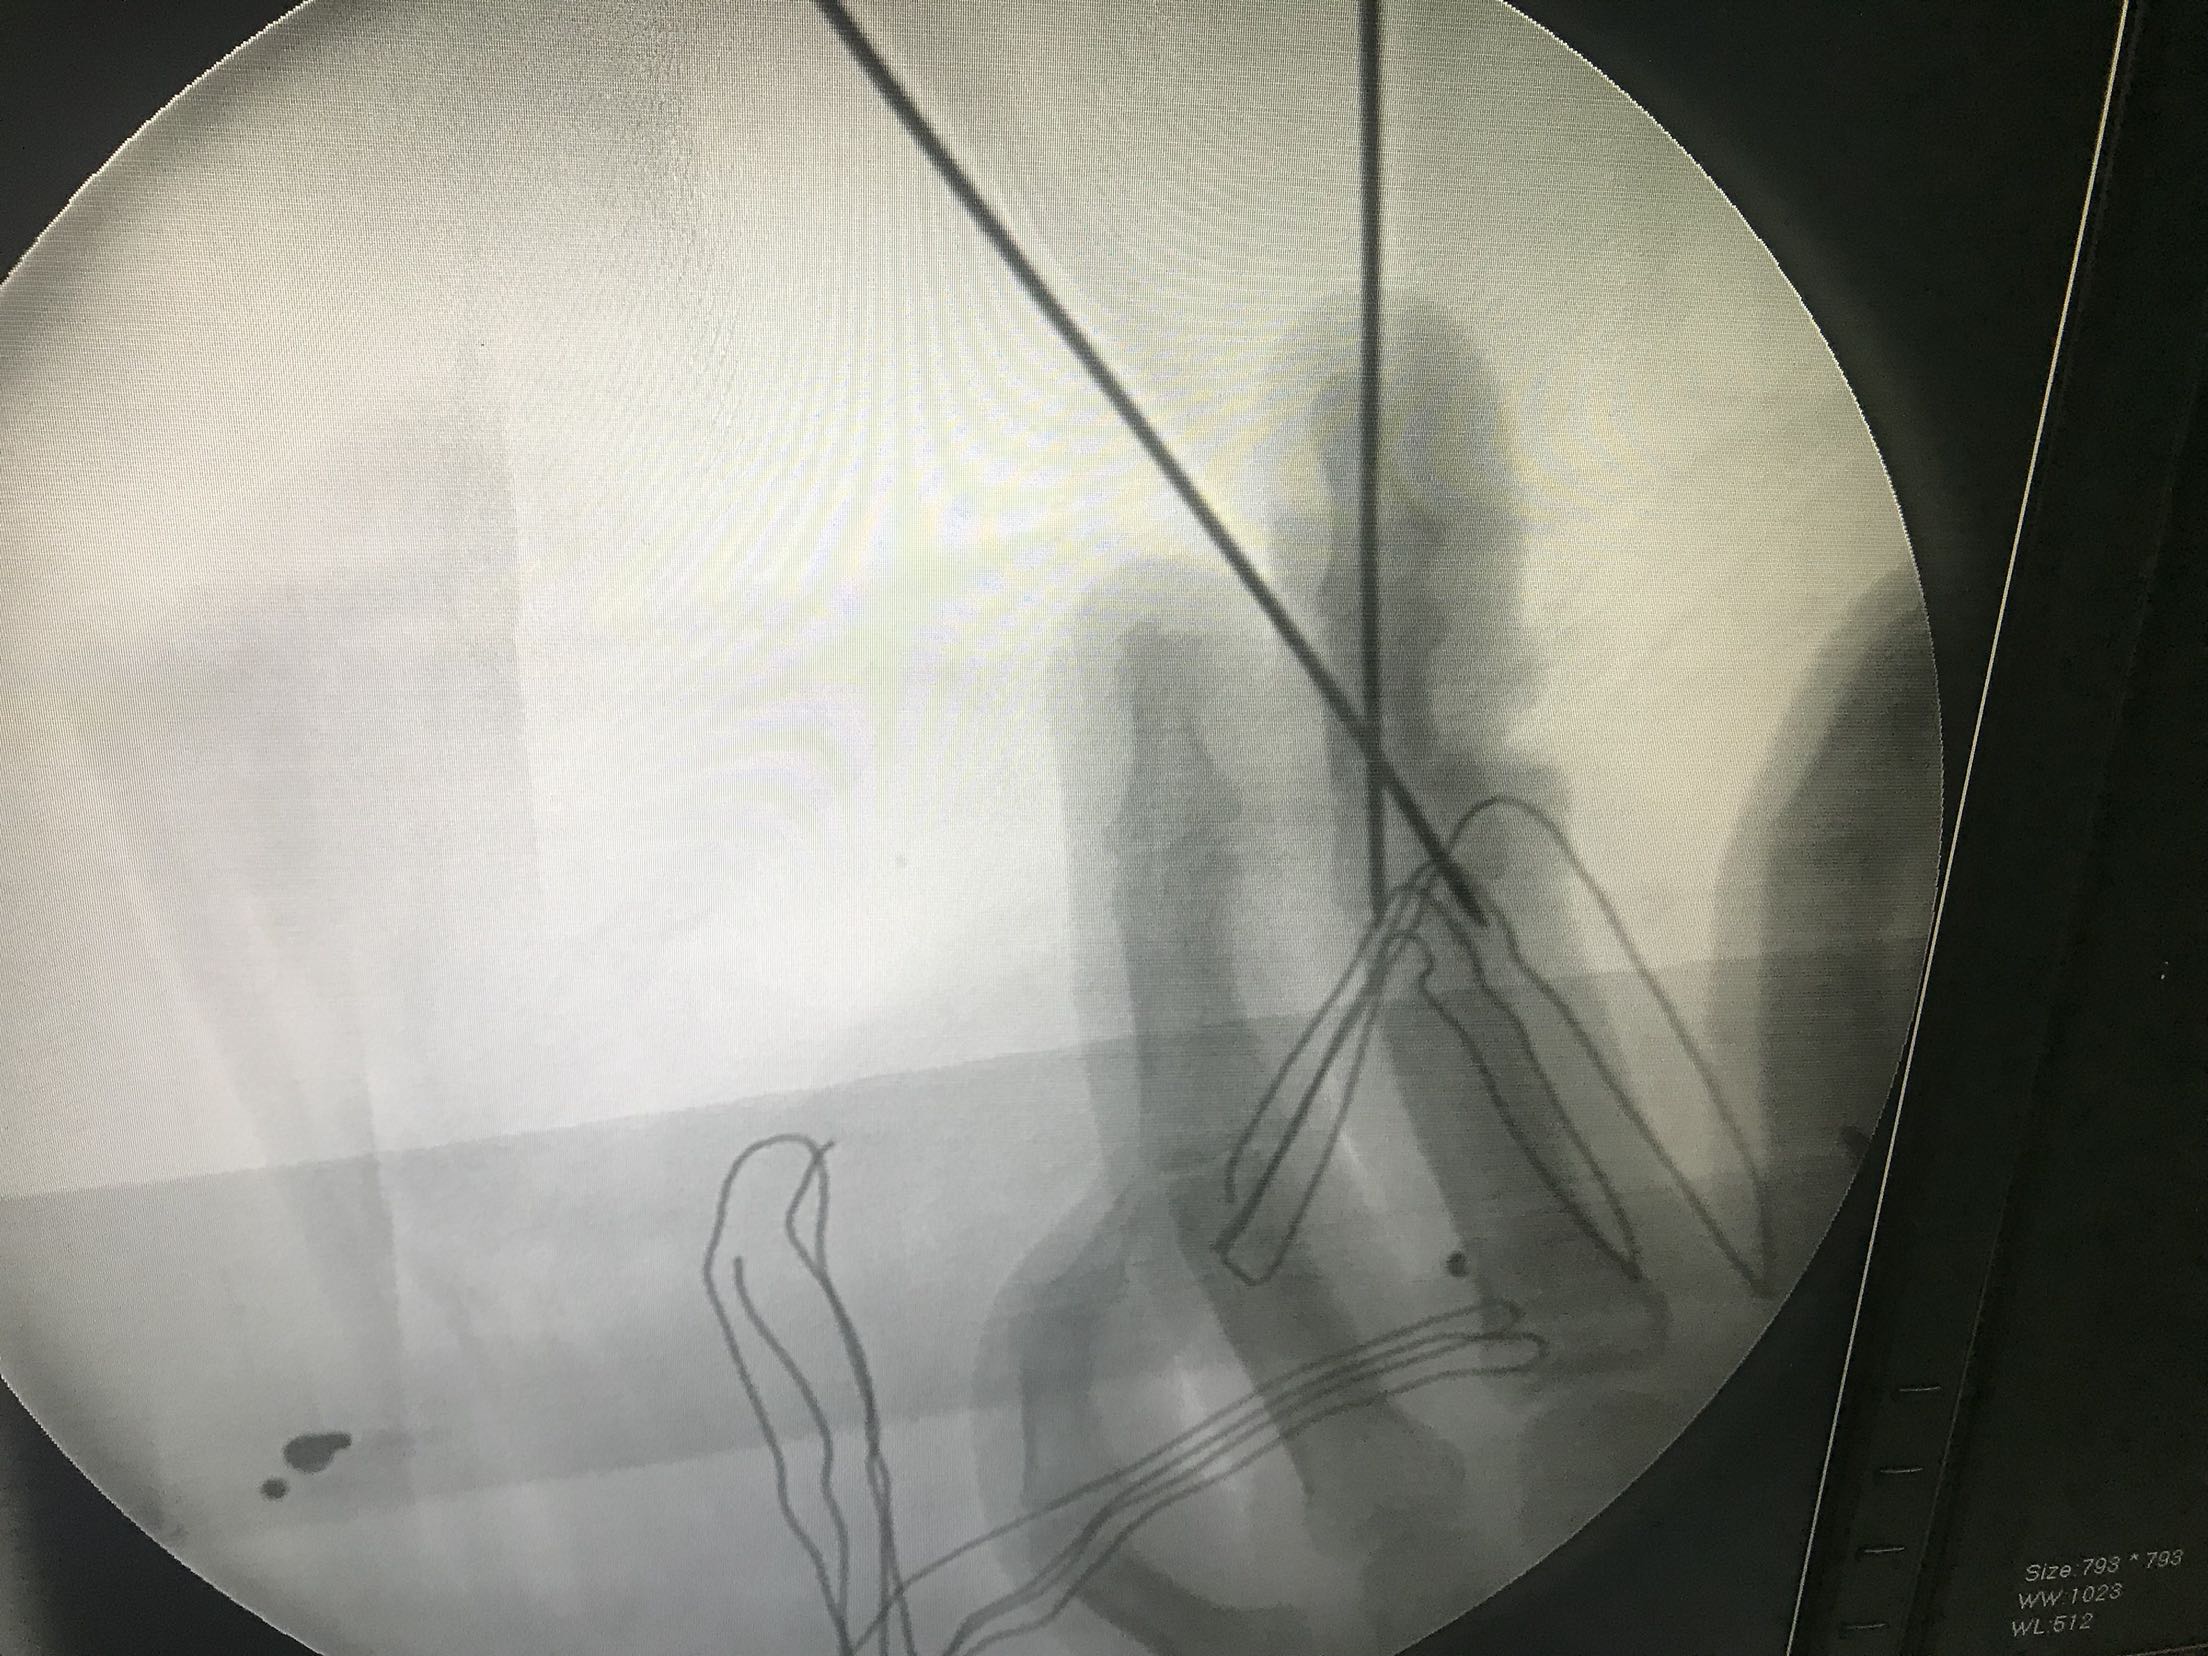

右手中指中节指体半环形锯齿状离断创口,创缘不齐,挫伤严重。仅尺侧部分皮肤软组织相连。离断指体颜色苍白,无血运,无温度,无感觉。

右手中指不全离断伤。急诊在臂丛麻醉下行右手中指试行再植术。术中适当短缩骨质,复位后克氏针内固定,修复屈伸肌腱,吻合双侧动脉神经。